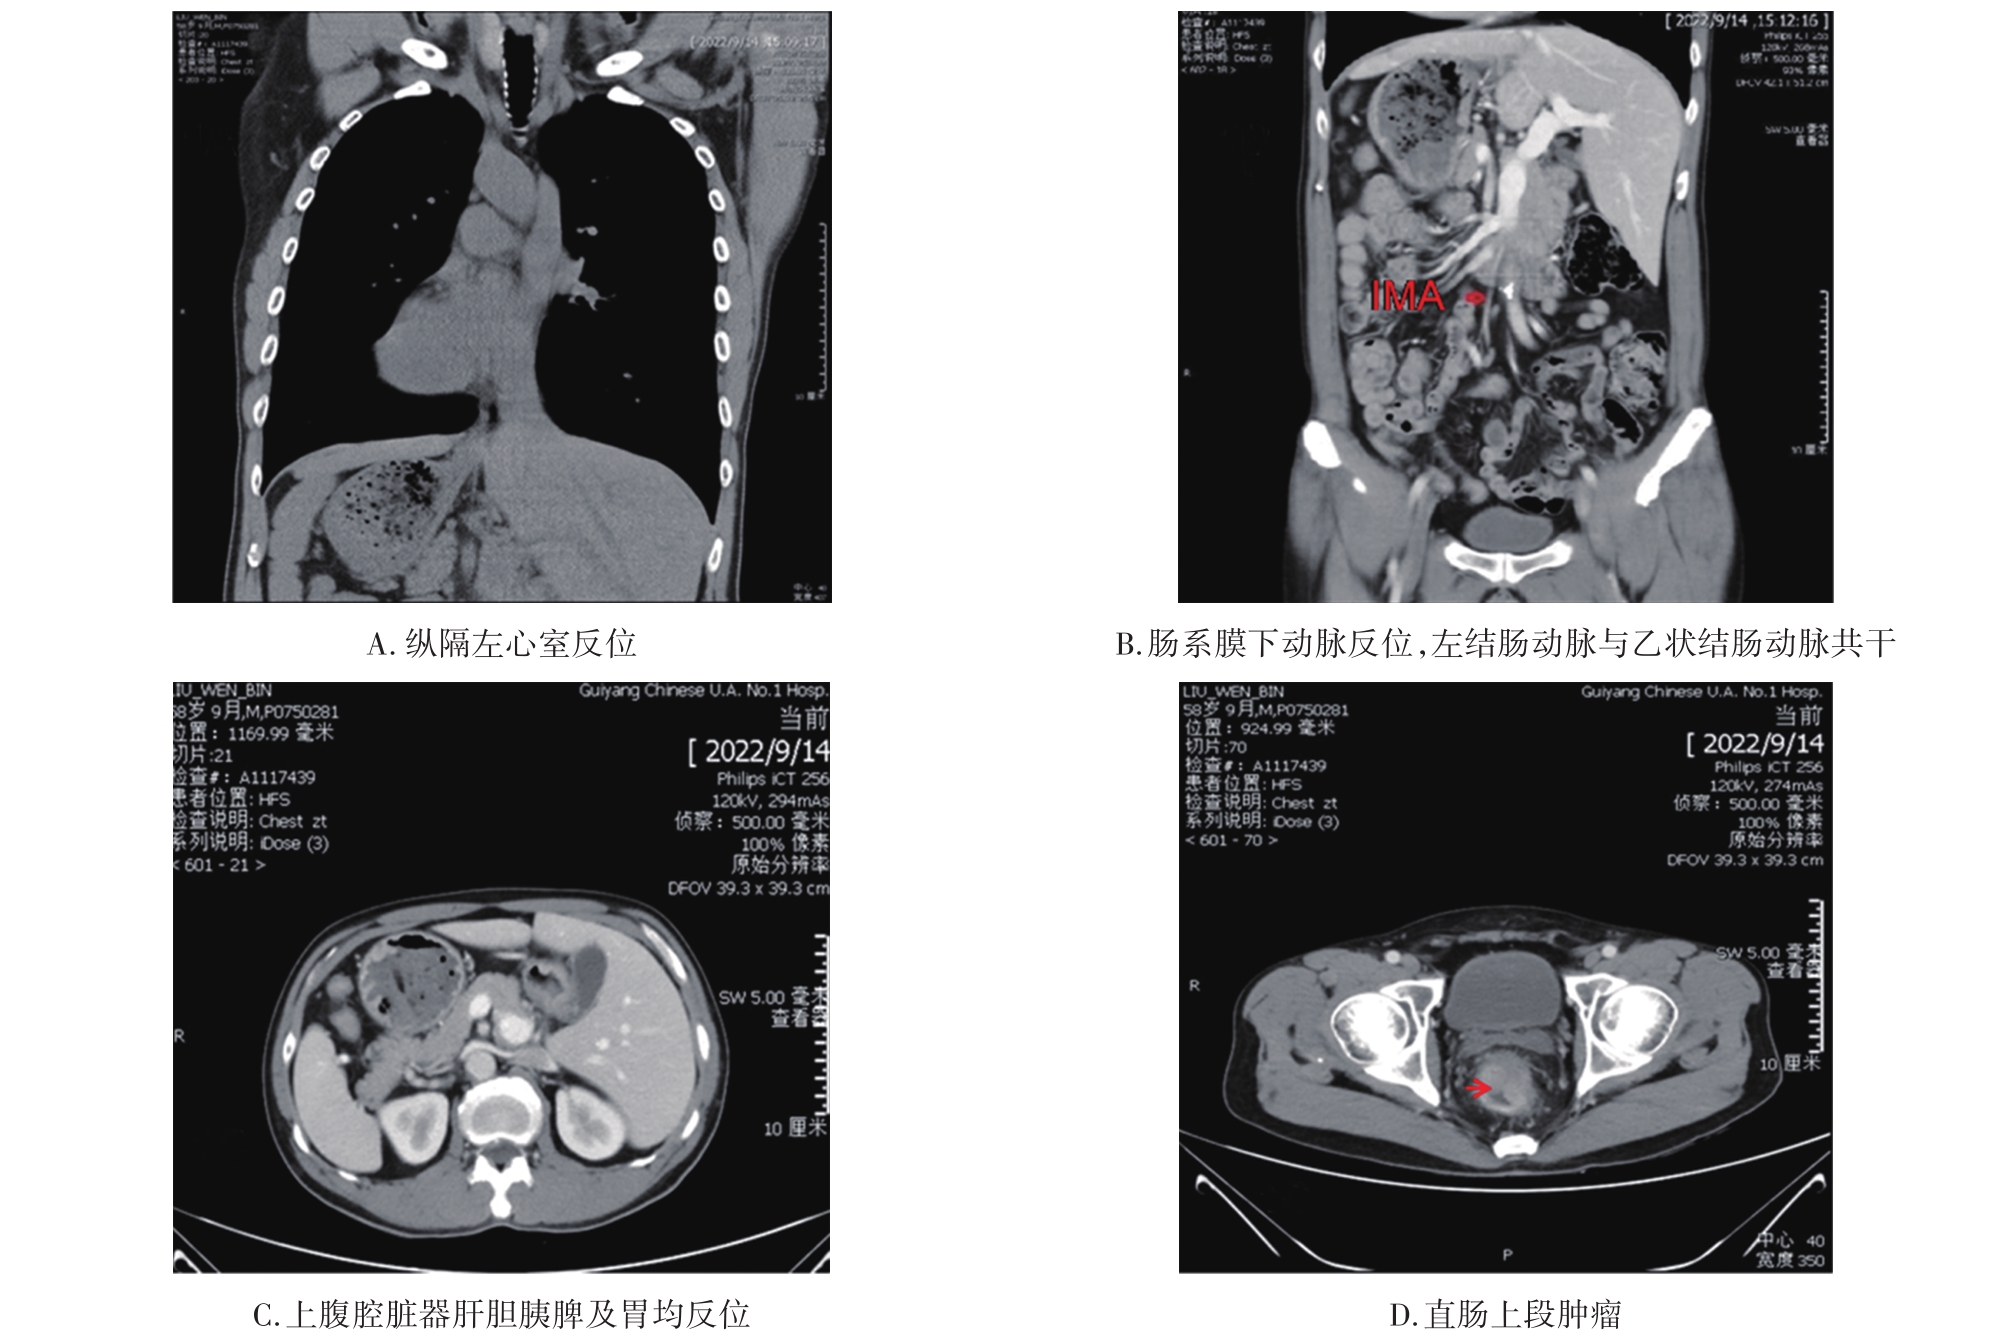

• “镜面人”保留左结肠动脉腹腔镜低位直肠癌根治术1例

2023, 48(7):853-856. DOI: 10.13406/j.cnki.cyxb.003278

摘要 (87) HTML (56) PDF 3.64 M (283) 评论 (0) 收藏